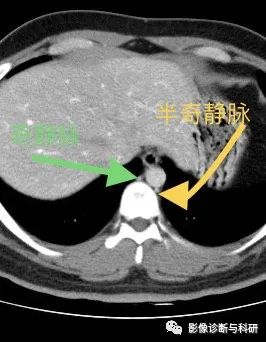

二、半奇静脉

是奇静脉的属支。半奇静脉起自左腰升静脉,沿胸椎体左侧上行,在食管、主动脉和胸导管的后方,达第8、9或10胸椎高处,然后向右横过脊柱汇入奇静脉。收纳左侧下部肋间后静脉、食管静脉、支气管静脉和副半奇静脉的静脉血。半奇静脉在门静脉性肝硬化时,对于交通上、下腔静脉,形成侧副循环有重要意义。